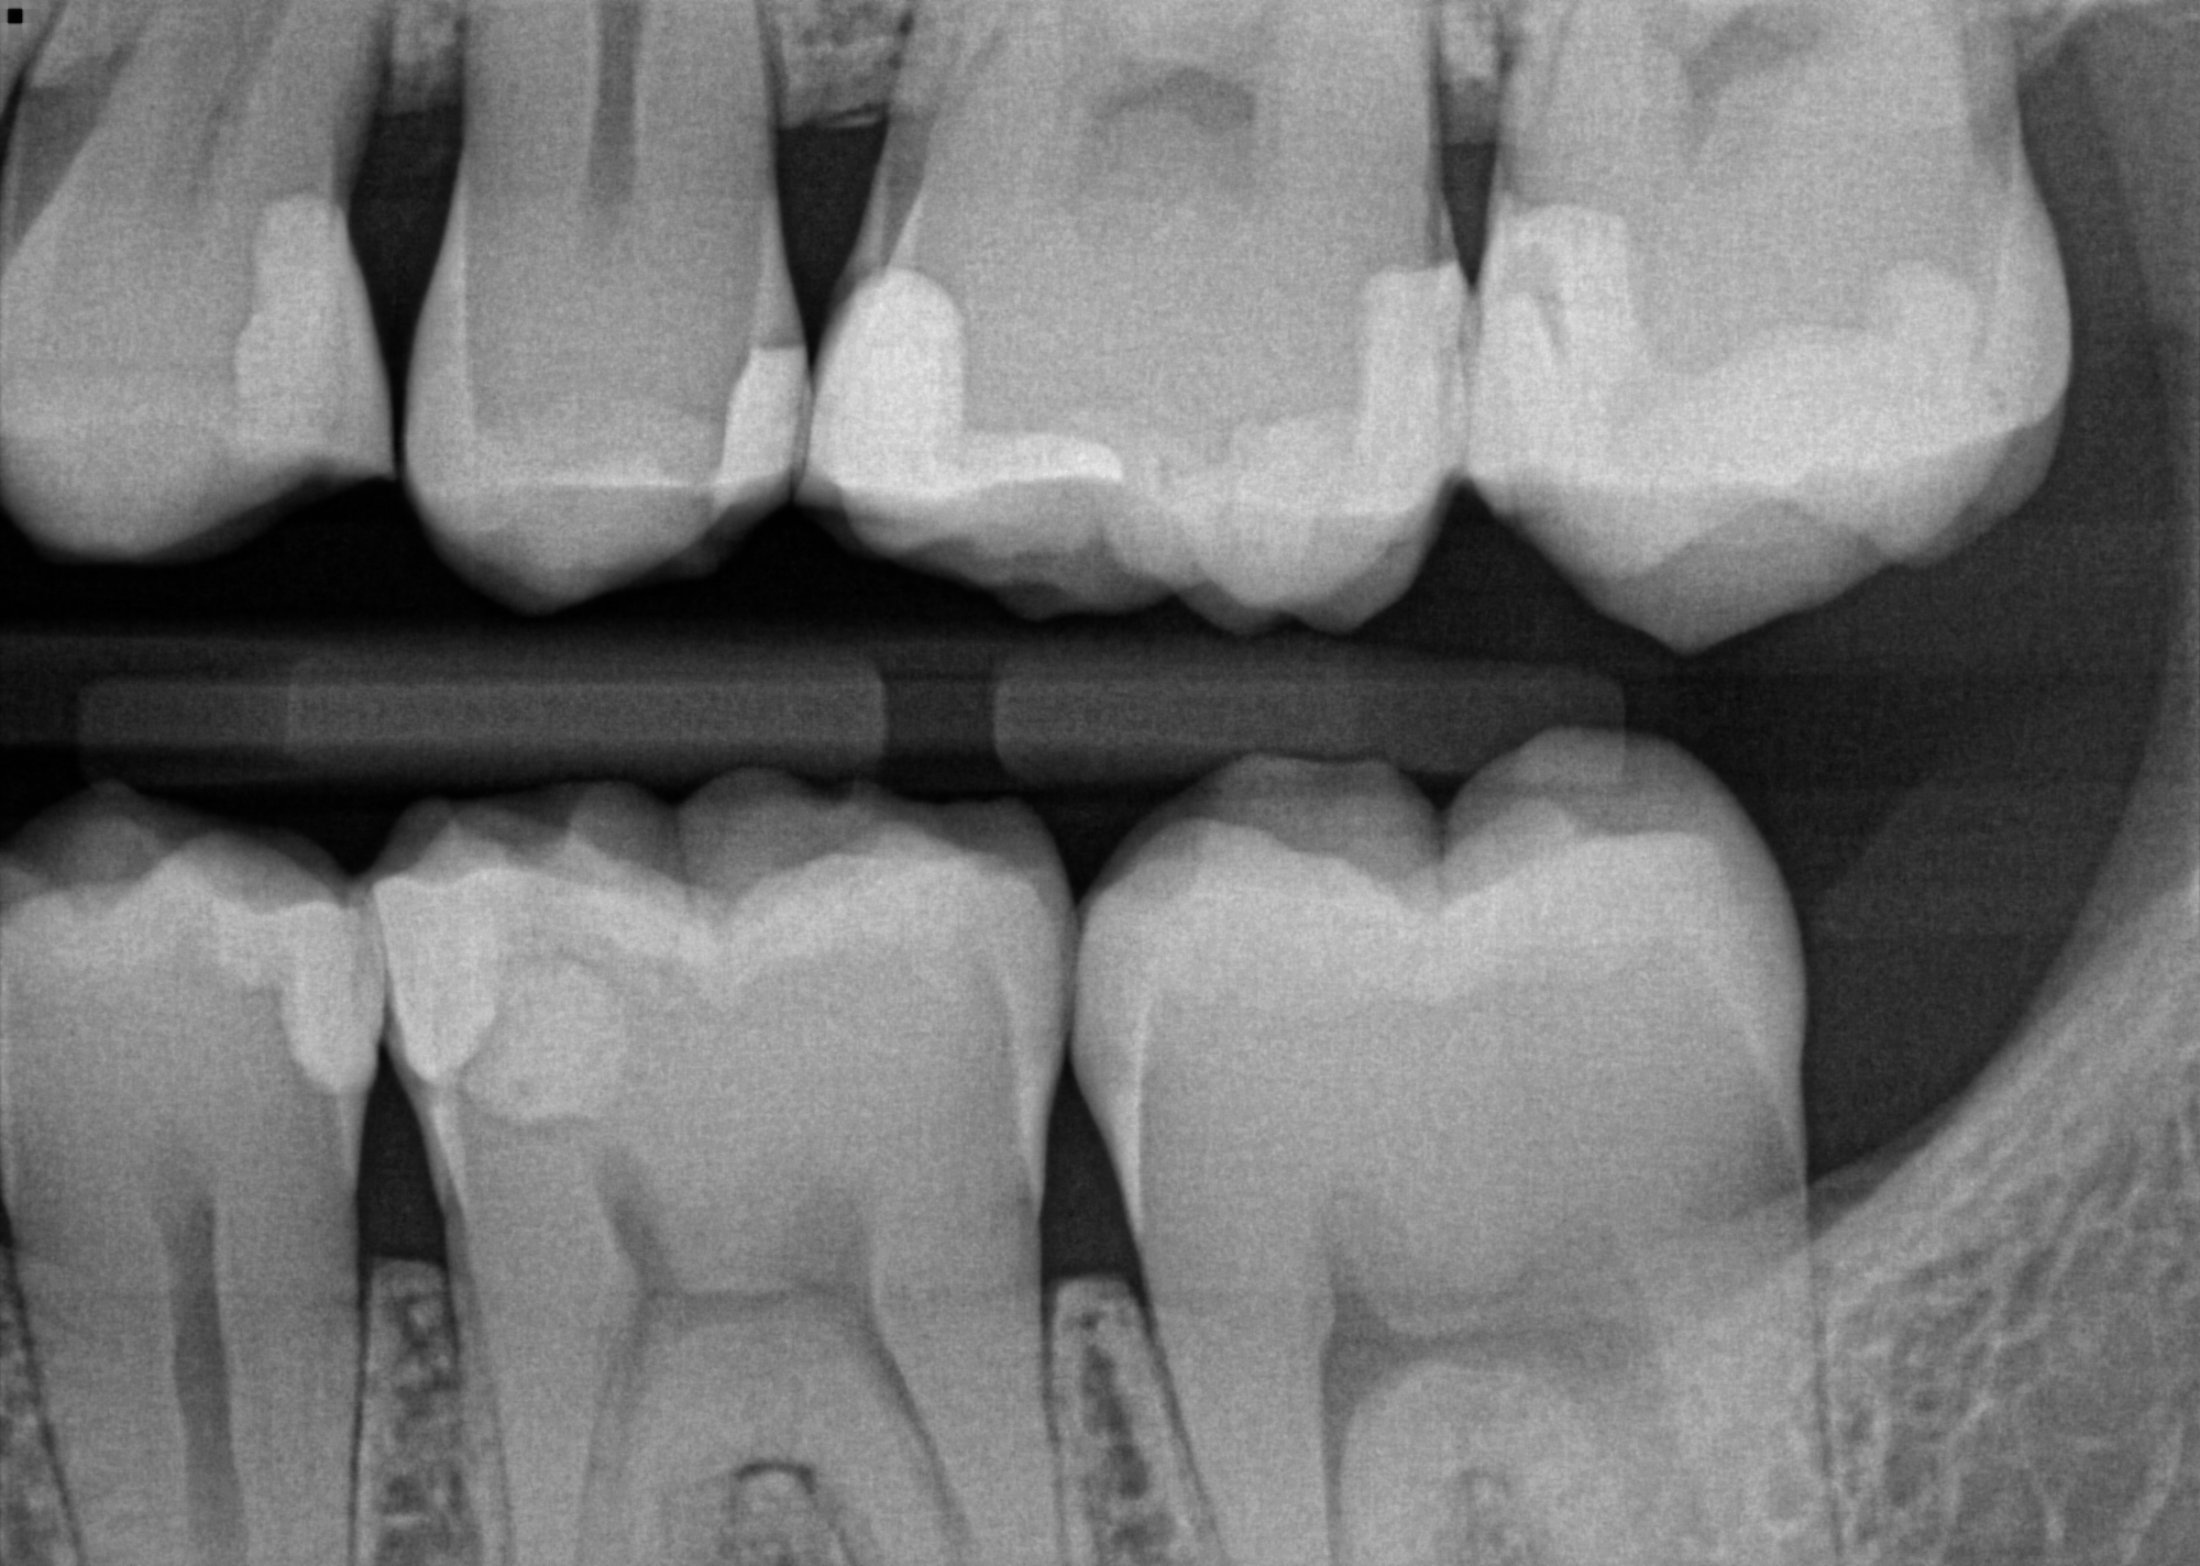

Examples of intraoral and extraoral bitewing radiographs. (a) Intraoral Ada Code Extraoral Bitewings The development of specialized panoramic radiograph machine software has spawned the introduction of an innovative and promising dental radiographic examination type: In a teledentistry encounter, how are image capture and. D0210 is typically paid once every three to five years. D0120 (periodic oral evaluation—established patient), d0140 (limited oral evaluation—problem focused), and d0150 (comprehensive oral evaluation—new or established patient). These diagnostic. Ada Code Extraoral Bitewings.